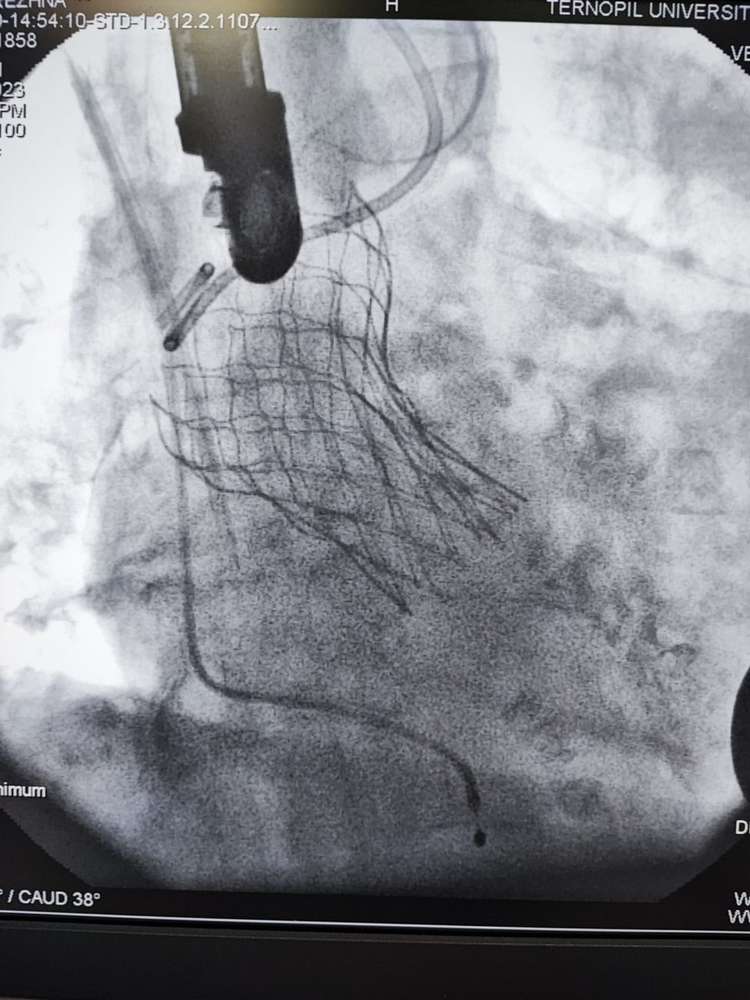

В Тернопільська обласна клінічна лікарня вперше виконано транскатетерну імплантацію аортального клапана через трансапікальний доступ.

Одна з пацієнток має важке викривлення хребта, і внаслідок цього анатомічно складне положення серця, аорти та інших внутрішніх органів, яке практично унеможливлювало виконання заміни клапану іншим доступом окрім трансапікального. Суть операції полягає в тому, що на працюючому серці виконується невеликий отвір, через який через трубку-катетер по провіднику вводиться згорнутий клапан, – йдеться в дописі.

Лікар додає, що позиціонування контролюється як рентгенівським зображенням так і черезстравохідним ультразвуковим датчиком.

Після імплантації хірург затягує вузол навколо отвору і ушиває рану. Крововтрата є мінімальною. Наша лікарня вже має досвід імплантації шести аортальних клапанів через стегнову артерію. А тепер освоїли і цю методику, яка має свої переваги в певній групі пацієнтів,- зазначив Богдан Маслій.